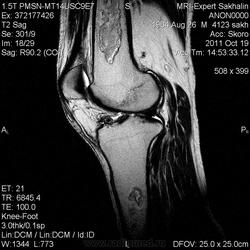

- В ранней стадии - остеопения и потеря трабекулярности костной ткани с окружающим склеротическим кольцом

- Участки склероза, образующиеся в зоне некроза кости, и формирование относительно новой костной ткани

- В поздней стадии - неравномерные участки затемнения или кальцинаты (изображение в виде морской гальки, гроздьев винограда, мишени или кольца), обычно расположенные на периферии

- Зона инфаркта кости может иметь длину до 20 см

- При инфаркте в области эпифиза языковидное или клиновидное затемнение распространяется от основания эпифиза на суставную поверхность.

b) Рентгенологическое исследование демонстрирует выраженный склеротический край и центральный участок снижения рентгенопрозрачности в дистальном отделе бедренной кости и в большеберцовой кости. Проксимальный отдел бедренной кости демонстрирует участок частичного грубого склероза, который иногда трудно отличить от энхондромы.